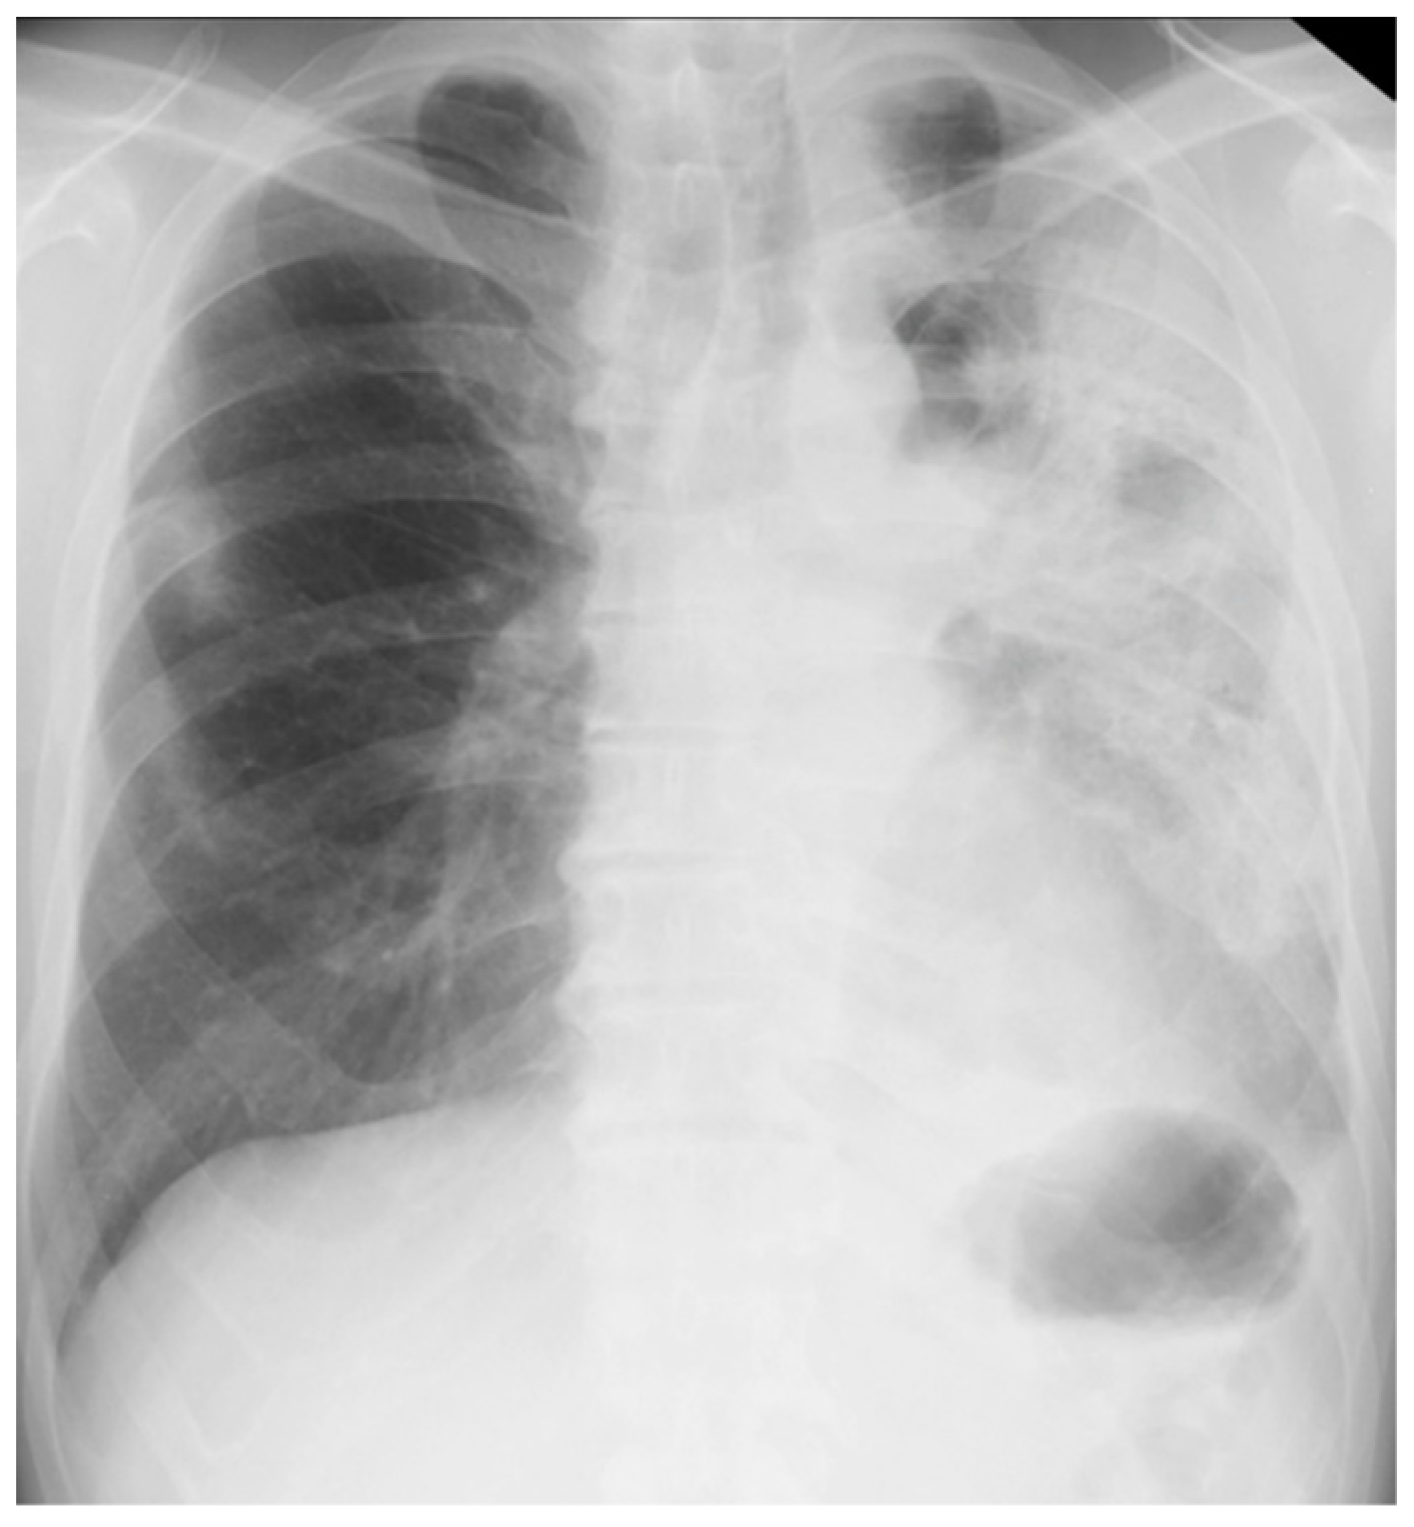

Her chest X-ray on admission showed consolidation in the bilateral peripheral-based upper lung fields and a typical radiographic pattern, i.e., “photographic negative of pulmonary edema” [3]. (Figure 1) Chest computed tomography (CT) revealed extensive ground-glass opacities in the left lung with contractile changes. Non-regional consolidation was scattered throughout the peripheral upper and middle lobes of the right lung (Figure 2).

Figure 1. Chest X-ray of 55-year-old woman upon admission with fever and dyspnea. It showed bilateral consolidation in her upper lung fields.